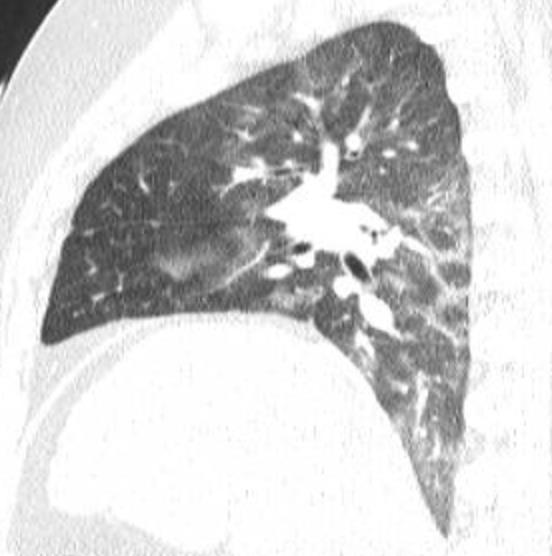

Acute Pediatric COVID-19: CT

21 Imaging of Covid 19 infection in children

3 Phases

Early: "Halo" sign

Local infection

Progressive: Diffuse GGO

Developed: Consolidation

Surr vasc congestion

Inflammation - adj alveoli

Alveoli fill with fluid/cells

Imaging of Covid 19 infection in children

Local infection Surr vasc congestion